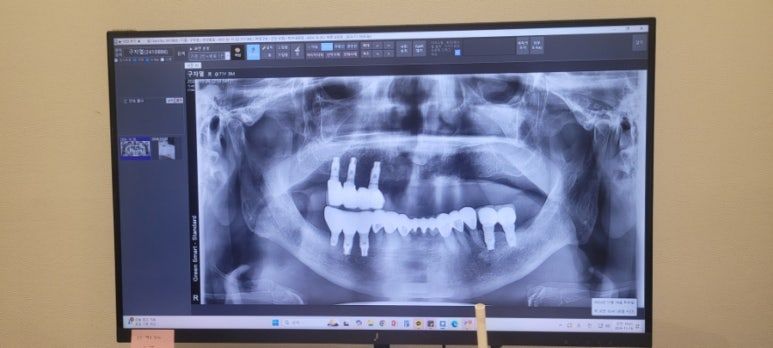

오늘 아빠는 6개 식립하고 엄마는 4개 식립하신다고 한다.

식립은 '인공치아 뿌리(임플란트 나사)를 턱뼈 안에 심는 과정이다.

보통 이를 뽑고 나면 그 자리가 비는데 그 빈자리에 인공치아의 뿌리 역할을 하는 쬐끄만 나사 같은 걸 턱뼈에 딱 박아서 고정하는 수술이 바로 '식립'이란다! 뼈에다가 심는다고 해서 '식립'.

마치 화분에 식물 심듯이 오늘 나사를 심는다고 한다.

오늘 지금 당장! 아빠는 6개 이빨 뽑으시고, 엄마는 4개 이빨을 뽑으신다니!!